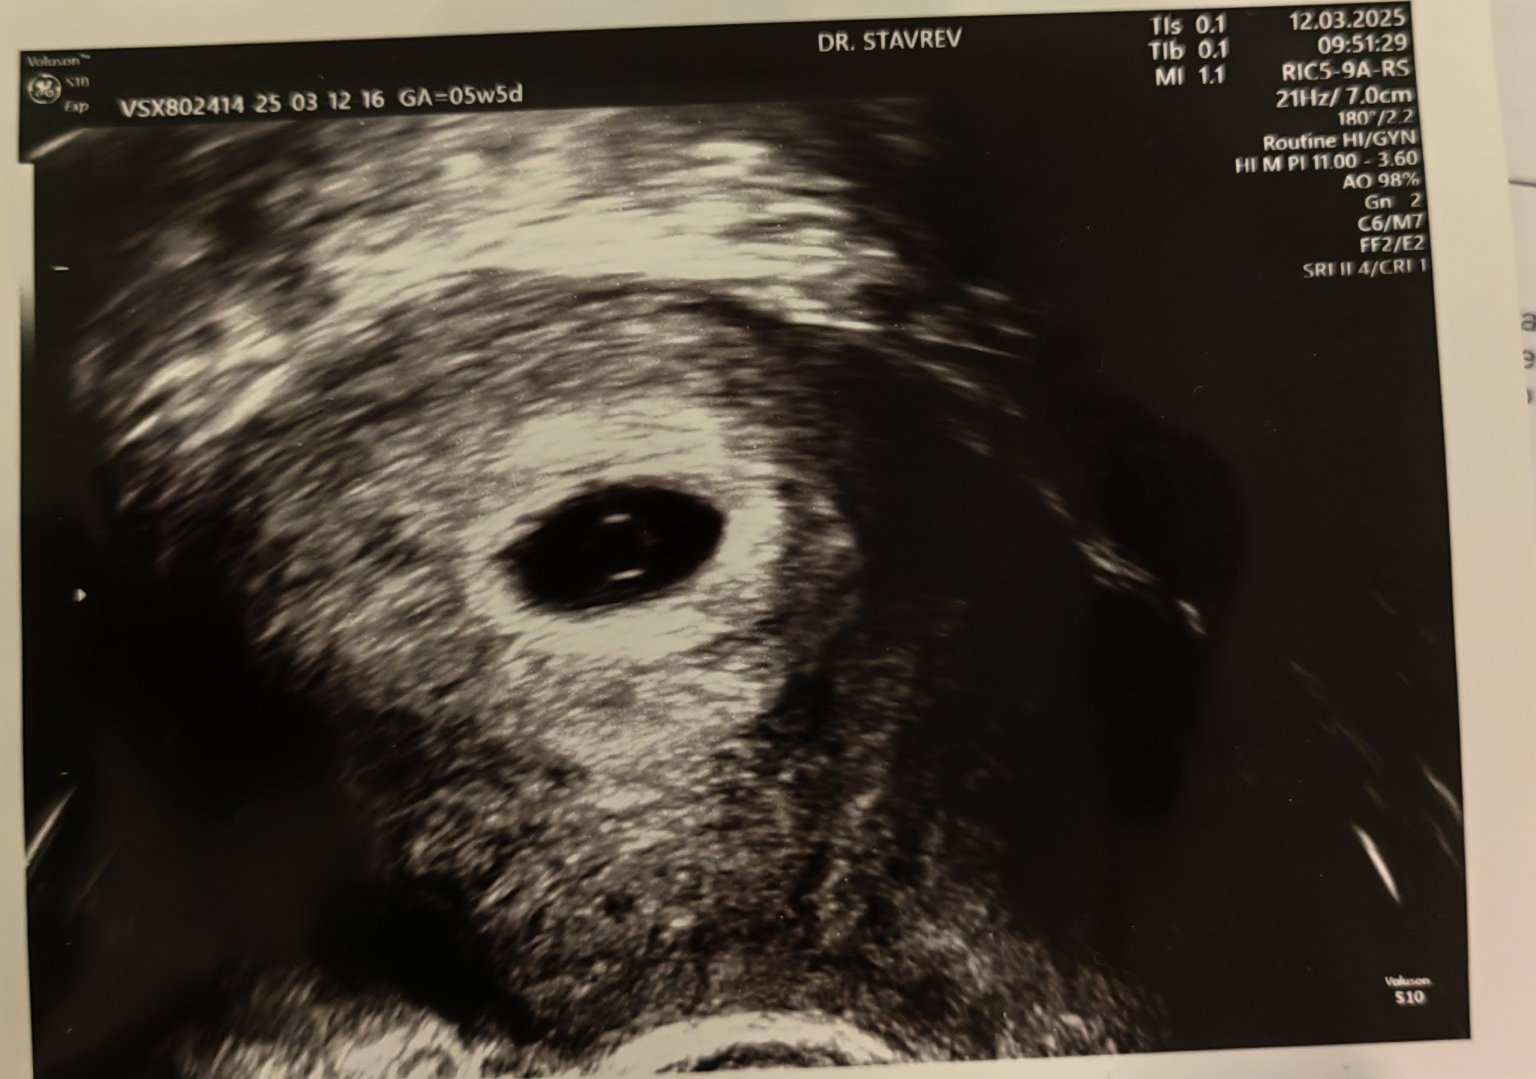

Какво представляват белите точки в плодния сак на ехографската снимка?